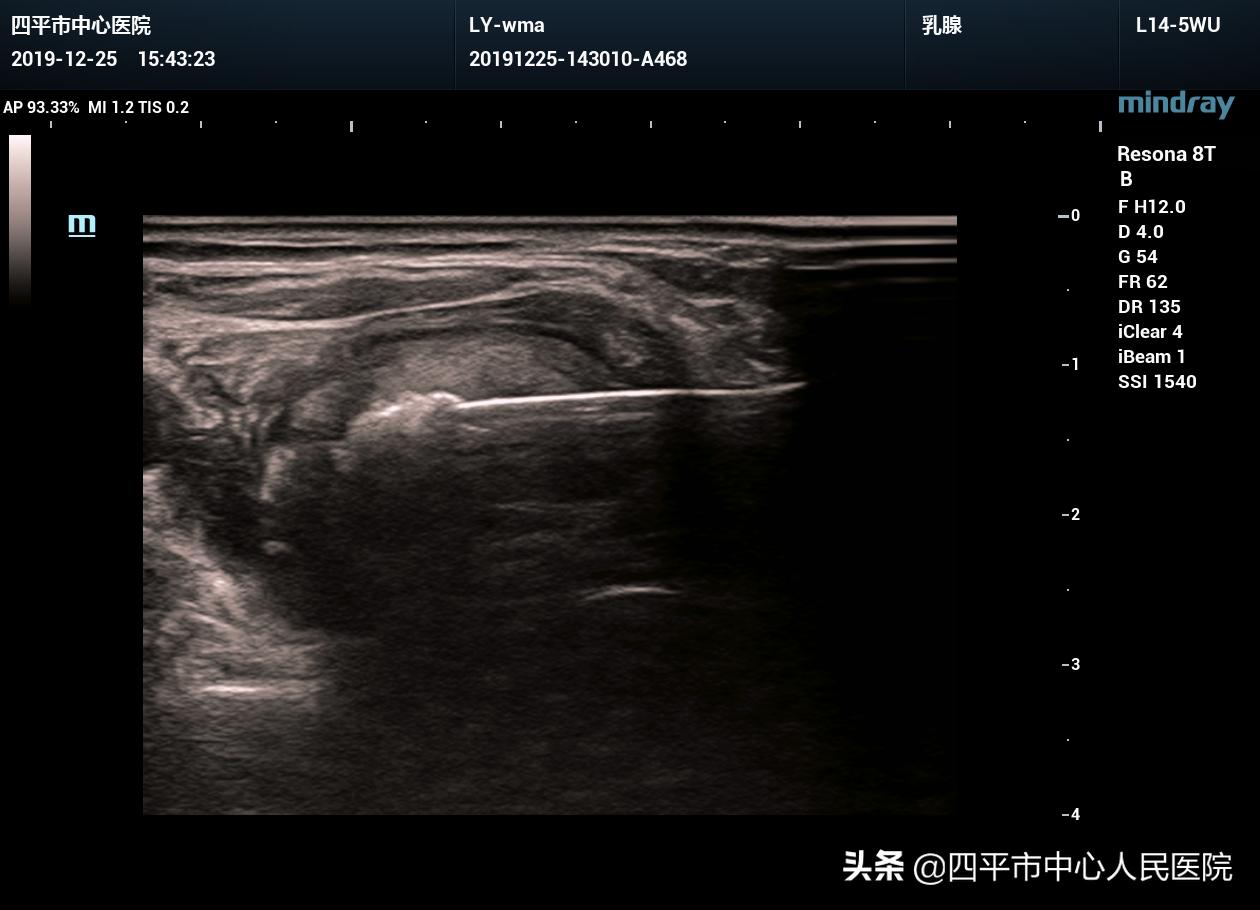

术中,局麻后,首先对结节内囊性部分进行抽吸酒精硬化治疗,然后置入微波消融针进行多点多切面消融,消融频率25W,消融后即刻进行超声造影,明确消融效果,造影显示消融区域未见明显强化,消融效果良好。

消融过程